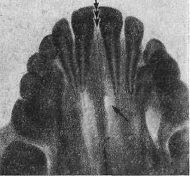

Рентгенография небного шва: Медицинские исследования и диагностика